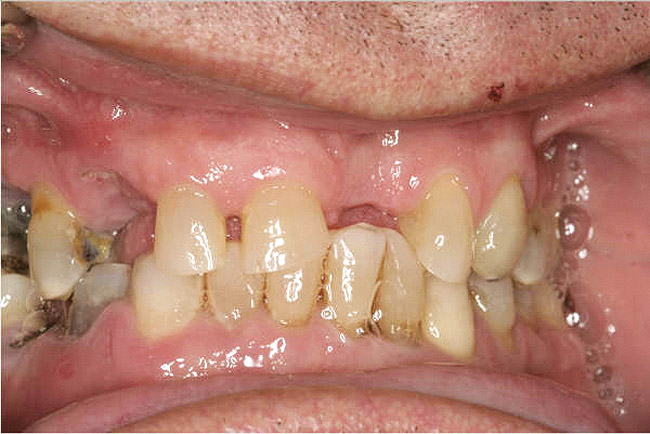

Figure 10a  Supra-eruption of the opposing arch, thus diminishing crown height space.

Figure 10a

Figure 10b  Supra-eruption of the opposing arch, thus diminishing crown height space.

Figure 10b